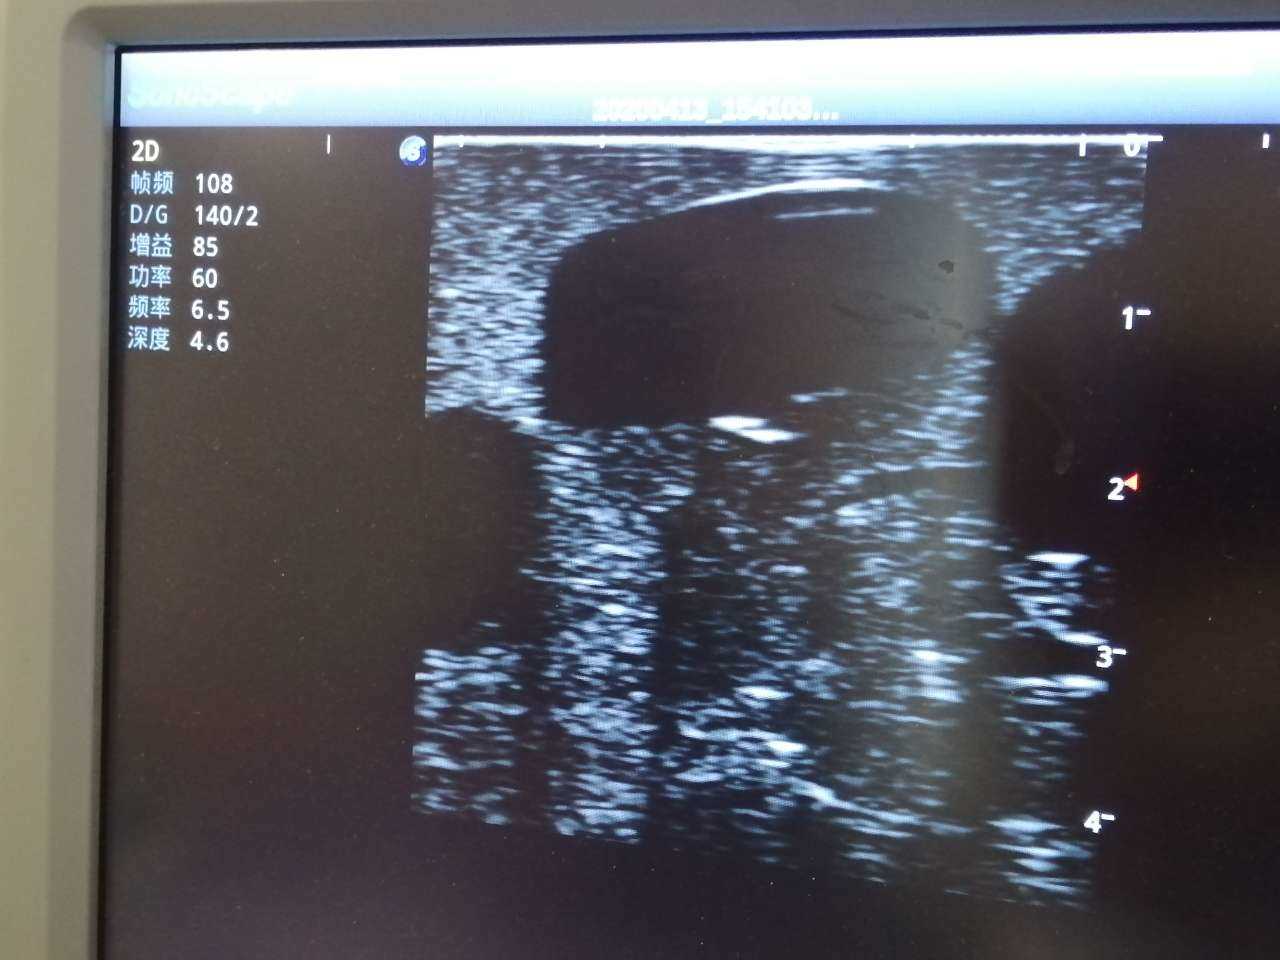

The trainer is designed for abscess ultrasound recognition, drainage, surgical cutting & suturing. With realistic landmarks and high-quality images, it’s an excellent choice for abscess-related skill training and practice.

· High-quality ultrasound images to show skin, soft tissues, abscess cavity and pus